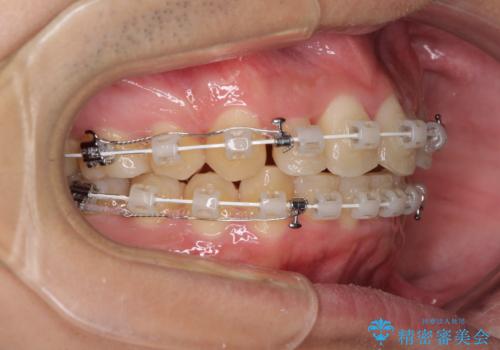

- 矯正装置

- 審美装置

咬合力が非常に強く、抜歯したスペースがなかなか閉じないであろうことは予想できましたが、思っていた以上に期間がかかりました。

前歯のすり減りも著しかったため、仕上げの位置の調整にも期間を要しました。